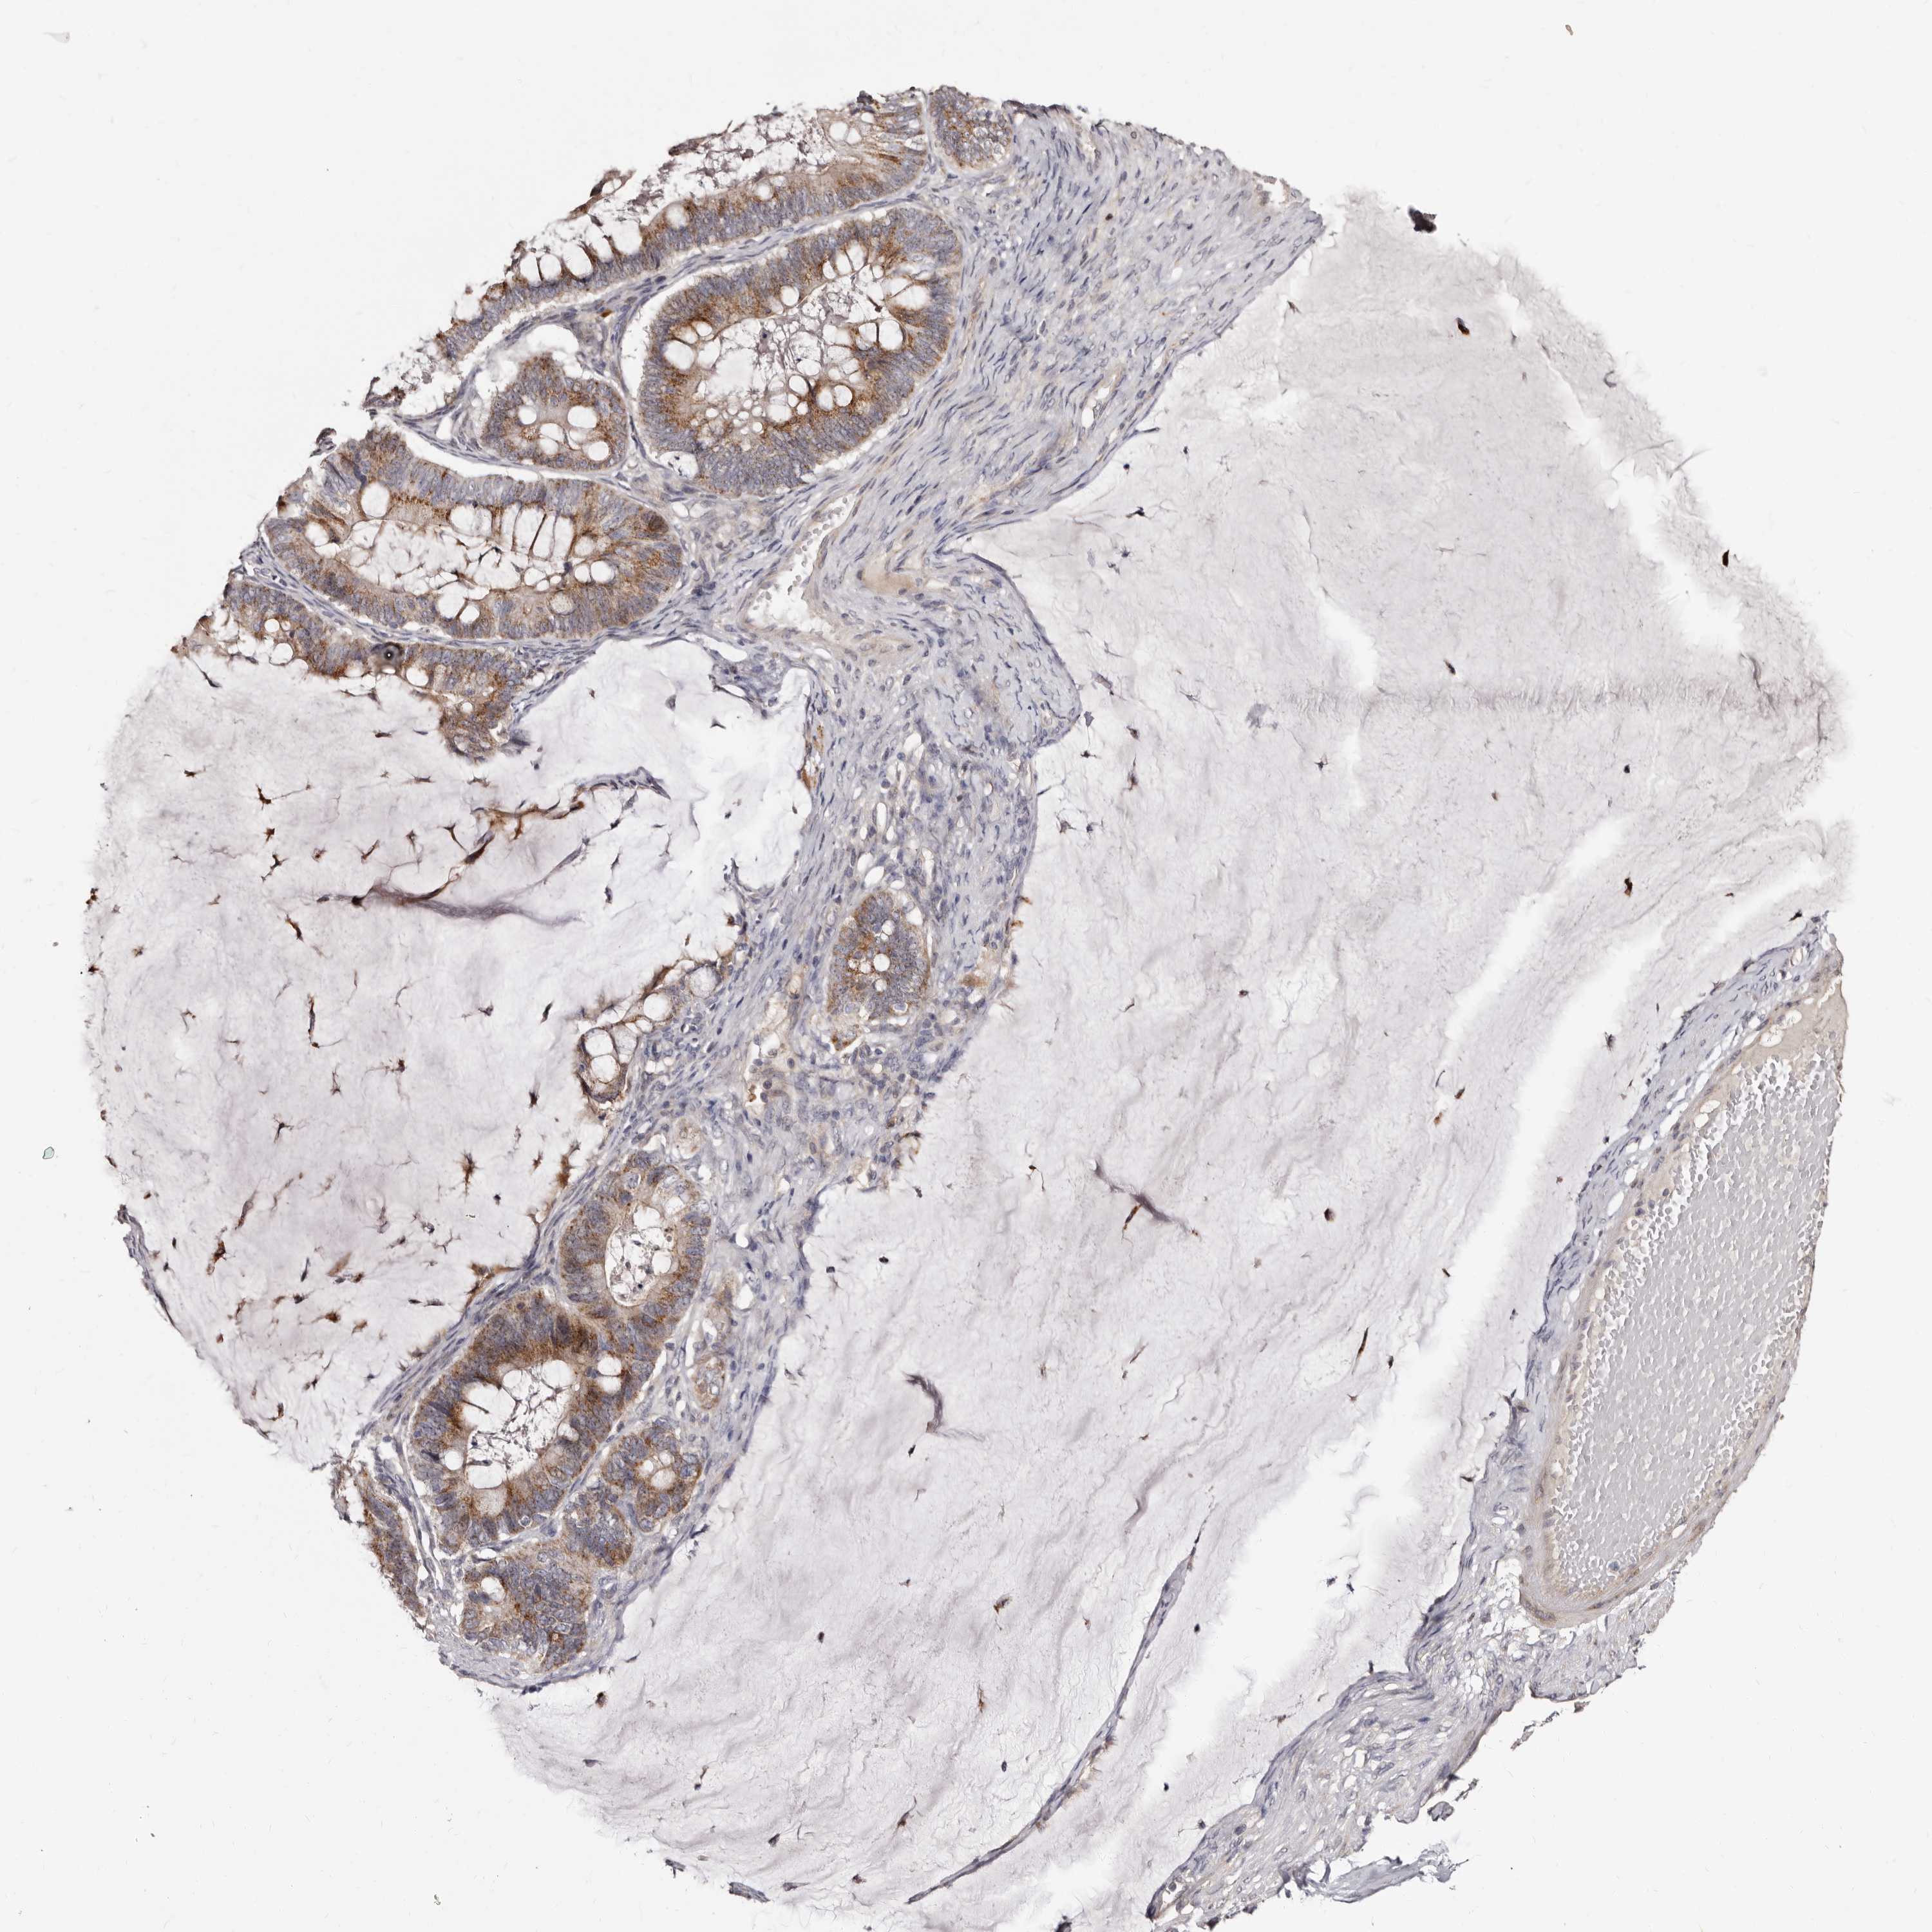

OVARIAN CANCER - Protein expressioni

A mouse-over function shows sample information and annotation data. Click on an image to view it in a full screen mode. Samples can be filtered based on level of antibody staining by selecting one or several of the following categories: high, medium, low and not detected. The assay and annotation is described here.

Note that samples used for immunohistochemistry by the Human Protein Atlas do not correspond to samples in the TCGA dataset.

Antibody stainingi

Antibody staining in the annotated cell types in the current human tissue is reported as not detected, low, medium, or high, based on conventional immunohistochemistry profiling in selected tissues. This score is based on the combination of the staining intensity and fraction of stained cells.

Each image is clickable and will lead to virtual microscopy that enables deeper exploration of all samples and also displays staining intensity scores, fraction scores and subcellular localization as well as patient and tissue information for each sample.

Antibody HPA027543

Staining

High

Medium

Low

Not detected

Intensity

Strong

Moderate

Weak

Negative

Quantity

>75%

75%-25%

<25%

None

Location

Nuclear

Cytoplasmic/membranous

Cytoplasmic/membranous,nuclear

Cystadenocarcinoma, serous, NOS

Carcinoma, endometroid

Cystadenocarcinoma, mucinous, NOS

Carcinoma, NOS